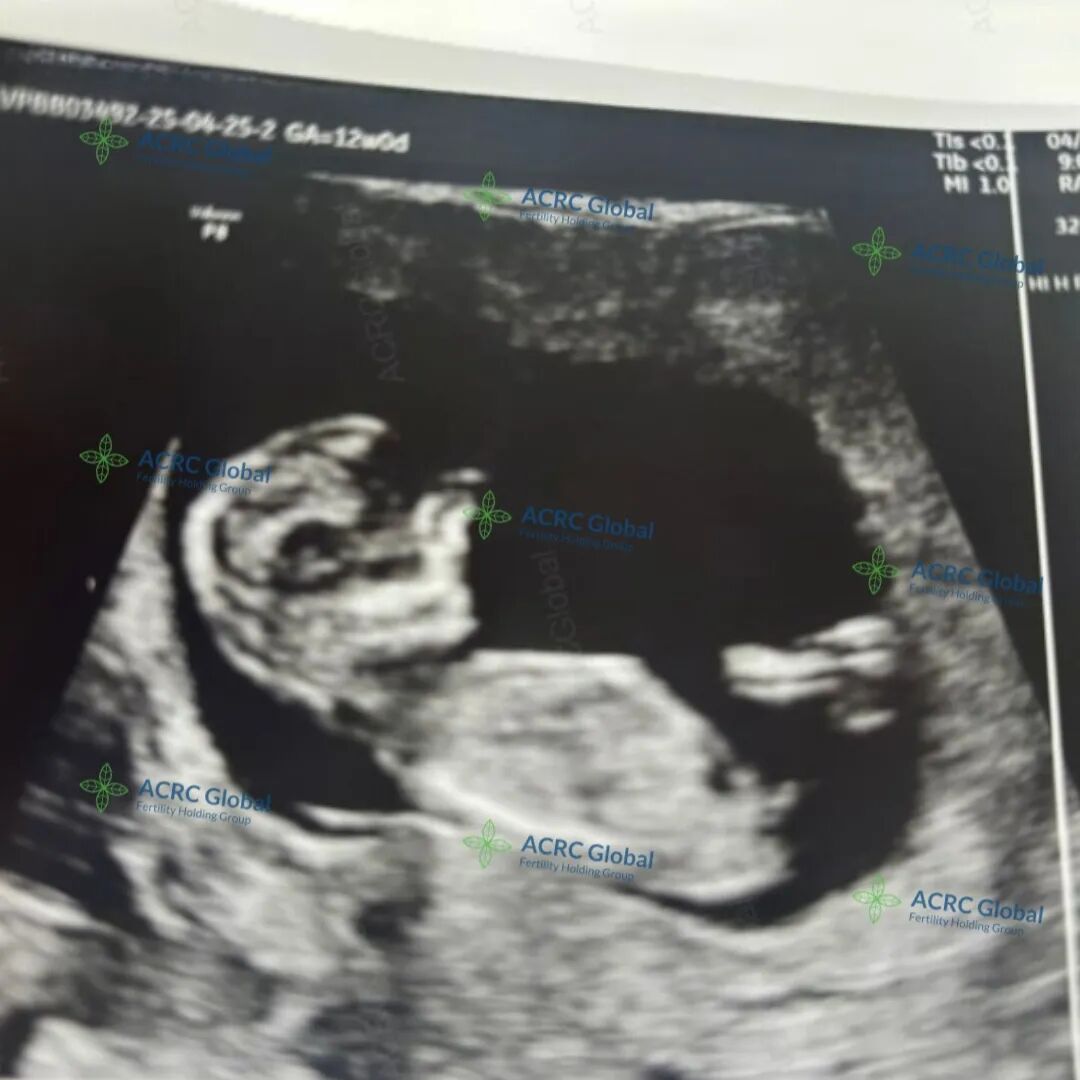

爱妈J的第二次孕期旅程正温柔而顺利地进行着,目前胎宝宝已满12周3天,胎心率高达172次/分,跳动着小小生命的蓬勃力量。这个阶段的宝宝已经初具人形,五官轮廓逐渐清晰,四肢也变得灵活,正在爱妈温暖的子宫中悄悄伸展、成长,每一刻都洋溢着勃勃生机。

这一次的宝宝,是准妈妈梦寐以求的小王子。在胚胎移植前,准父母特别选择了在美国应用广泛的PGT(胚胎植入前遗传学筛查)技术,对胚胎进行了全面的染色体筛查。这项技术不仅显著降低了遗传疾病的发生风险,也在法律允许范围内进行了性别筛选,实现了XY优选。于是这个被期待已久的男宝宝,如愿而至!我们也满心期待着,迎接他闪亮登场的那一天!